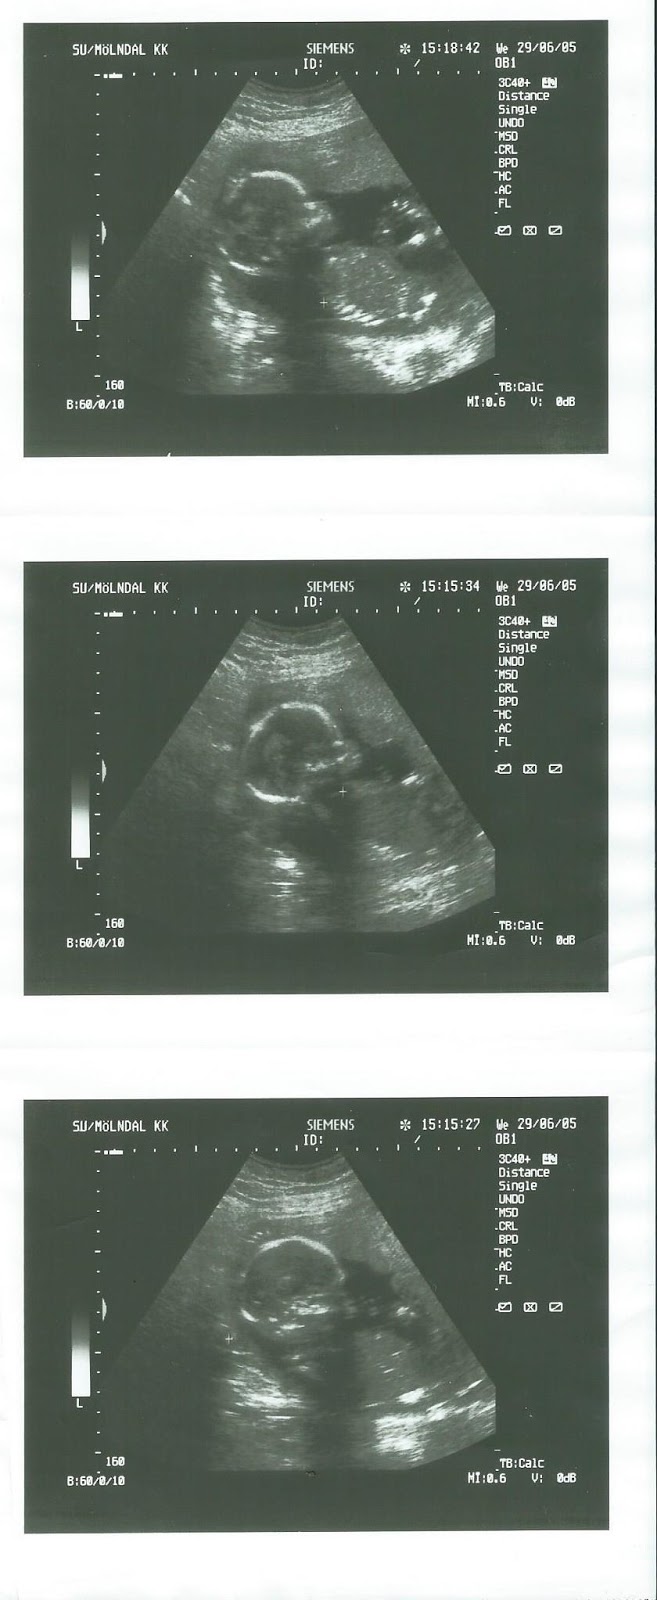

29 juni 2005

v 18

Äntligen var det dags för rutin ultraljudet och det var så spännande att få se sitt lilla barn, var lite orolig eftersom pappans syster fött två barn med hydrocefalus (vattenskalle) och att på min morfars sida föddes fyra av fem syskon döva.

Men allt såg jättefint och bra ut och vi fick hem tre bilder på vår lilla bebis som var så efterlängtad och älskad.